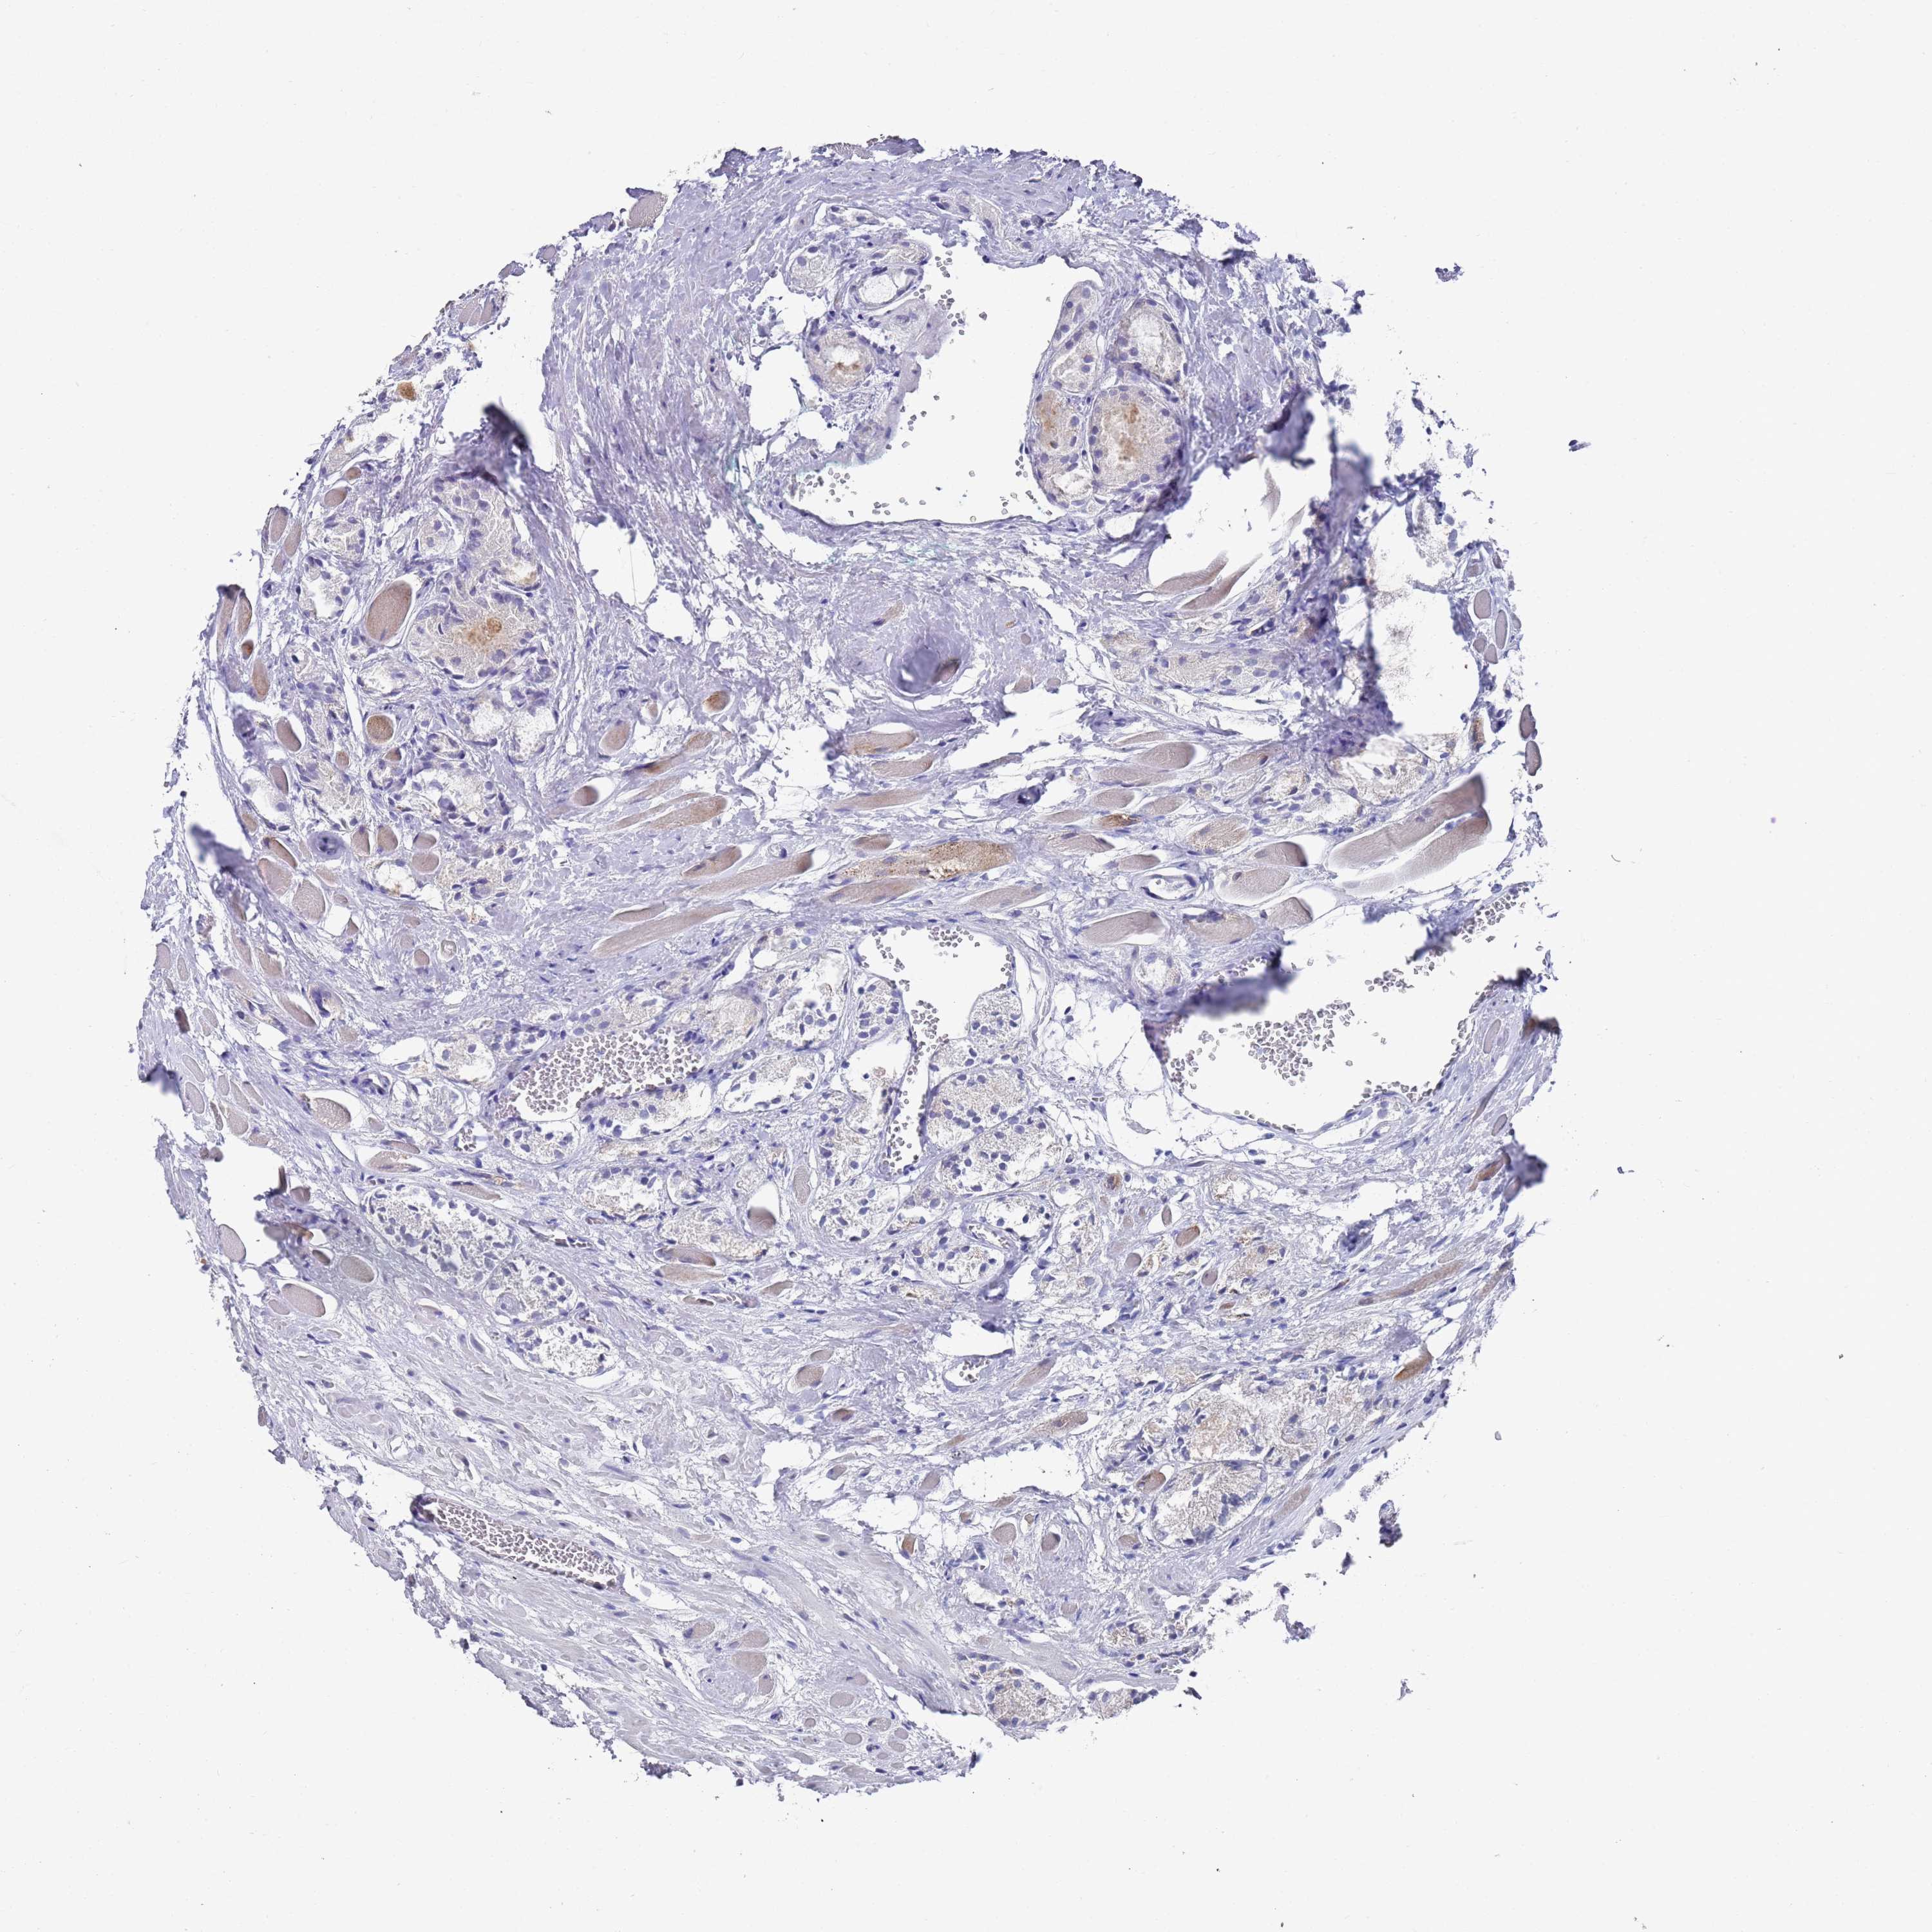

PROSTATE CANCER - Protein expressioni

A mouse-over function shows sample information and annotation data. Click on an image to view it in a full screen mode. Samples can be filtered based on level of antibody staining by selecting one or several of the following categories: high, medium, low and not detected. The assay and annotation is described here.

Note that samples used for immunohistochemistry by the Human Protein Atlas do not correspond to samples in the TCGA dataset.

Antibody stainingi

Antibody staining in the annotated cell types in the current human tissue is reported as not detected, low, medium, or high, based on conventional immunohistochemistry profiling in selected tissues. This score is based on the combination of the staining intensity and fraction of stained cells.

Each image is clickable and will lead to virtual microscopy that enables deeper exploration of all samples and also displays staining intensity scores, fraction scores and subcellular localization as well as patient and tissue information for each sample.

Antibody HPA021453

Antibody HPA045649

Staining

High

Medium

Low

Not detected

Intensity

Strong

Moderate

Weak

Negative

Quantity

>75%

75%-25%

<25%

None

Location

Nuclear

Cytoplasmic/membranous

Cytoplasmic/membranous,nuclear

Adenocarcinoma, NOS

Adenocarcinoma, High grade

Adenocarcinoma, Low grade